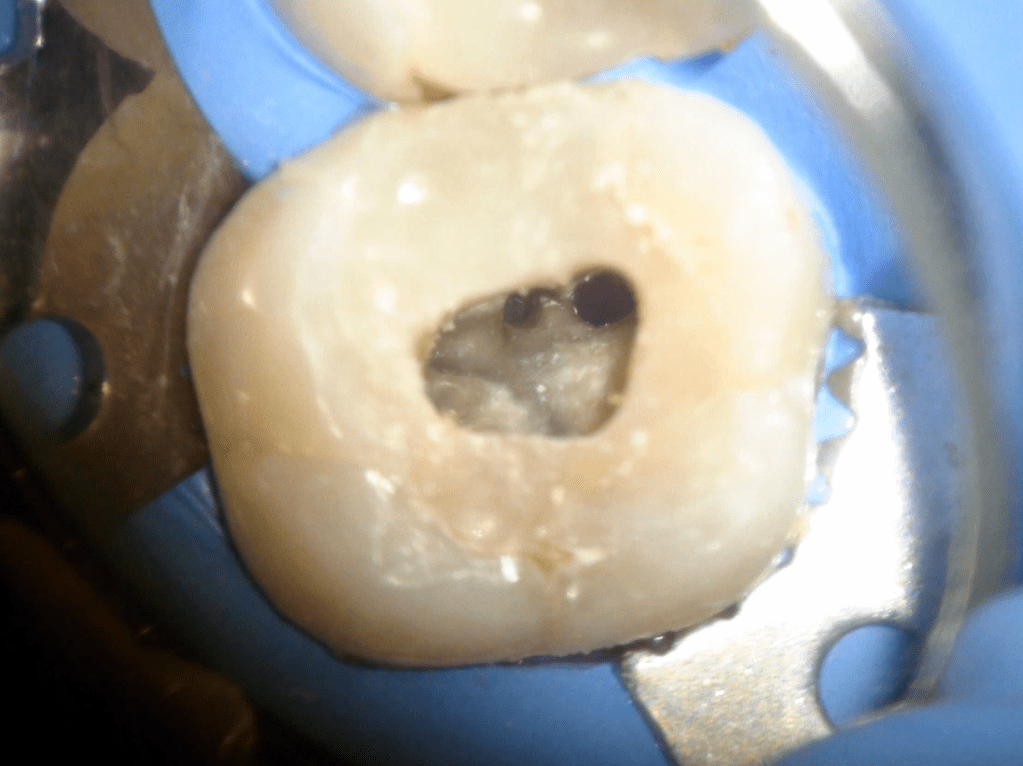

Acceso ultraconservador a través de incrustación reciente